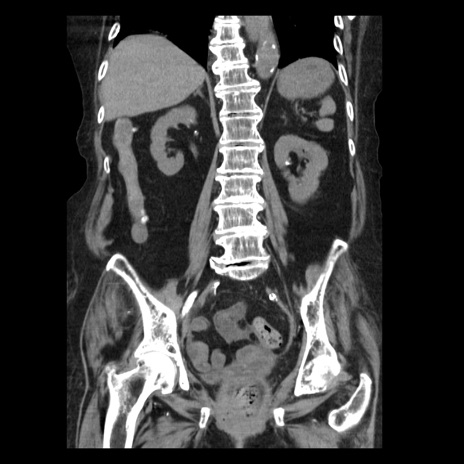

症例14(冠状断像)

【症例】 90歳代女性

【主訴】 腹痛・嘔吐

【現病歴】今朝から左側腹部痛を認めた。 経過観察していたが、嘔吐を認めたため来院。

【既往歴】 子宮癌術後

【身体所見】 意識清明、BP 127/54mmHg、P 98bpm Sp02 95%(RA)、BT 35.8°C、腹部平坦・軟腸ぜん動音聴取良好、右下腹部圧痛(+) 反跳痛なし

【データ】WBC 9800、CRP 0.46